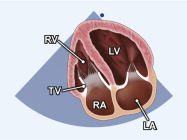

| 2.6. Mặt cắt trục dài cạnh ức qua buồng nhận thất phải |

||||||||

|

|

Cửa sổ siêu âm cạnh ức

Mặt cắt trục dài cạnh ức Ngả đầu dò xuống dưới hướng về phía đùi phải của bệnh nhân |

Nhĩ phải (RA) Van ba lá (TV) Thất phải (RV) |

|||||